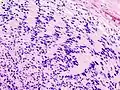

Schwannome mélanotique

C'est une tumeur rare. Elle s'intègre, dans 50 % des cas, dans le complexe de Carney (myxomes cardiaques, pigmentation lentigineuse faciale, anomalies endocriniennes). Il existe au sein de la prolifération d’abondantes mottes de mélanine ainsi que des psammomes (en). Les cellules tumorales expriment la PS100 et l’HMB45 (marqueur de différenciation mélanocytaire).